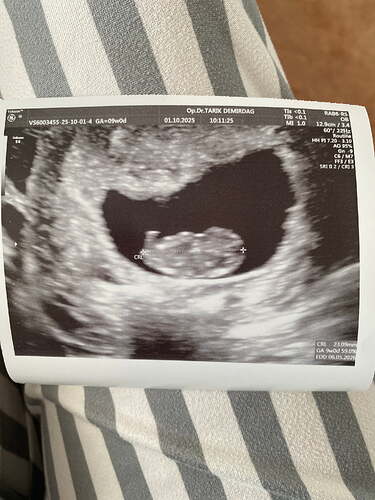

Sizce ney ![]()

![]()

Kese sekli gozukmuyor ki yakından kafa gozukuyor sadece. Uzaktan var mi